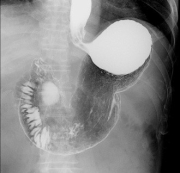

X線透視検査

X線透視撮影装置でX線を連続的に使用しリアルタイムで状態を観察し、撮影を行います。

造影剤を使用した消化管検査(胃透視、注腸造影)や嚥下造影をはじめとし、脱臼や骨折の整復・固定、内視鏡と併用した治療も行います。

主な検査

上部消化管検査

下部消化管検査